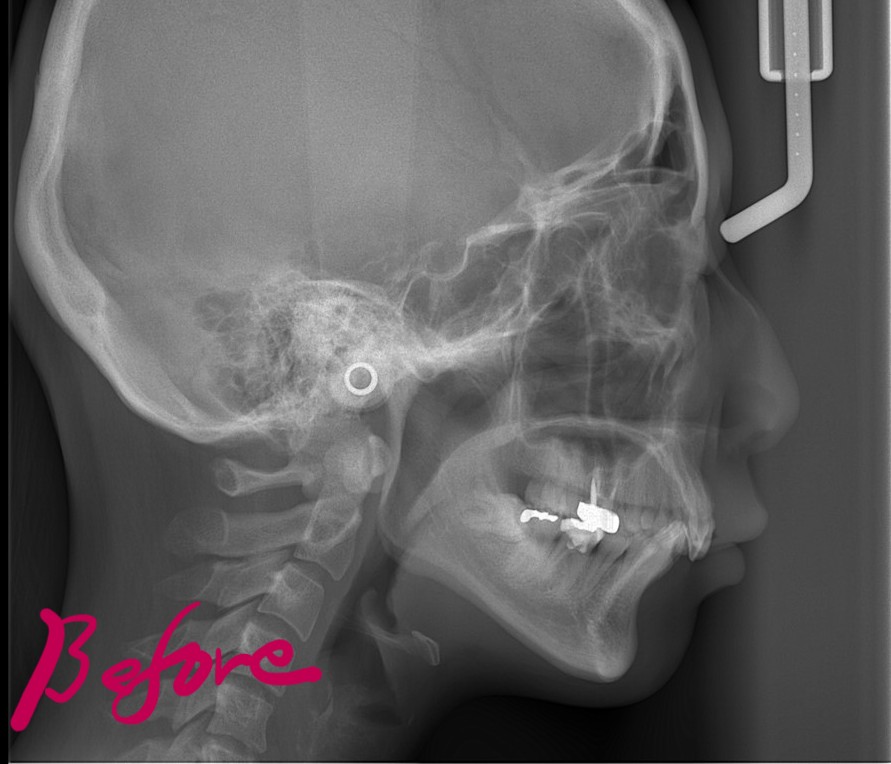

【Before】

レントゲン写真を確認すると、

この患者さんの場合、